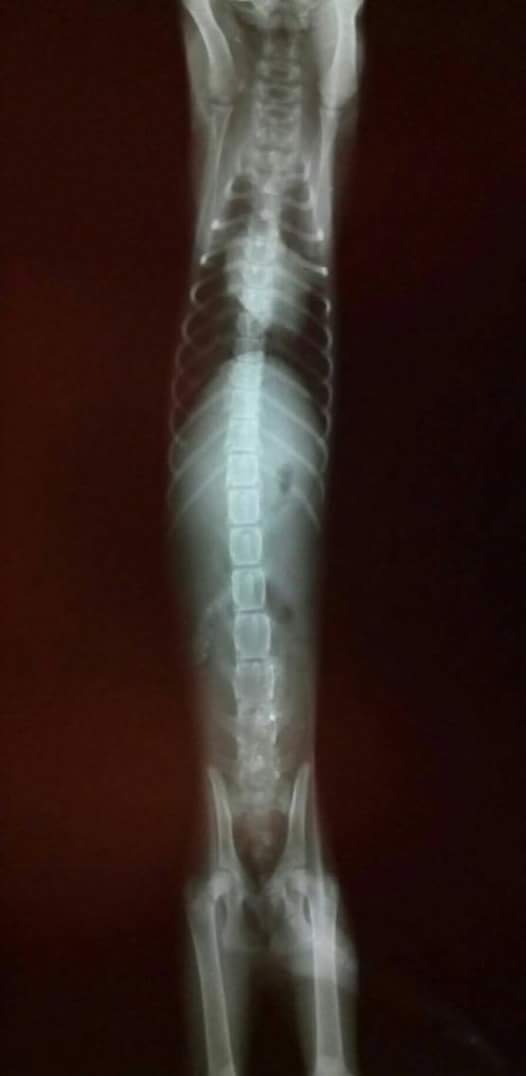

主題: 車禍腦震盪昏迷不醒的小橘子 申請者姓名: 張菱予 花色: 申請日期: 2016-05-30 19:16:49 申請者部落格: 申請者臉書網址: http://www.facebook.com/clyanal 所在縣市/合作醫院: 高雄市/小新動物醫院 治療費用: 3700元 需求人數: 9人 已結案 (2024-06-01 13:35:45) 報名人員: Cary x2(已付款)、Chang tzu lan x2(已付款)、Hamigua(已付款)、馬羅姐姐 x2(已付款)、Pond Kao x2(已付款)、 候補人員: 動物病情說明: 今天晚上我在下班回家途中發現馬路中間有一隻被車撞倒在地上抽蓄的小幼貓,目測右眼球腫脹凸出,身上有擦傷,我抱著沒有意識的他,立刻送往離當時最近有TNR配合的小新動物醫院,因為到院時小橘子昏迷不醒,醫生趕緊先打止血點滴,因小橘子失溫且昏迷,需觀察2~3天後看生命跡象是否穩定,經檢查小橘子的後腳仍有知覺,但還無法判斷能不能行走。因為我目前中途許多幼貓尚未送養,平時救援開銷就不少,所以沒有能力再負擔車禍小橘子的醫療費用,所以車禍小橘子的費用只好請協會幫幫忙。未來這2~3天還是危險期,小橘子才大約兩三個月大,希望他能挺過難關趕快好起來! 動物近況說明: 小橘子到院時非常虛弱,稍微清醒時醫生趕緊幫他做血檢X光檢驗等等,隨後打了降腦壓針劑治療,小橘子晚間仍持續昏迷不醒,經歷一天的治療隔天小橘子仍宣告不治。當他躺在車陣當中時真的很心痛,立即送醫希望能救他一命,沒想到撞擊力道太大,小橘子熬不過危險期,希望他快樂的去當小天使,也謝謝協會和幫助小橘子醫療費用的大家。